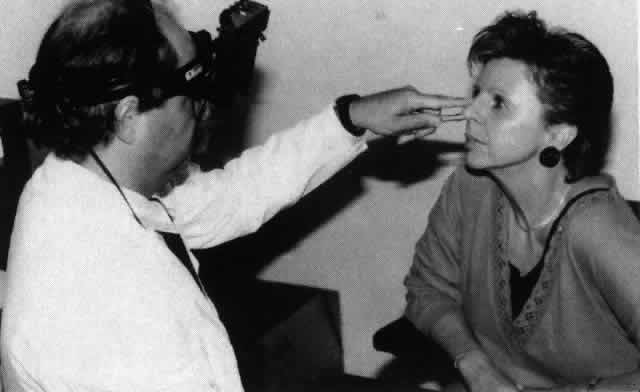

Forced Duction Test

The forced duction test is a useful test for distinguishing paralytic strabismus from restrictive strabismus. The forced duction test is used to detect an inelastic extraocular muscle that prevents the globe from rotating. For example, a tight inferior rectus muscle will not allow the globe to rotate superiorly. The test is carried out by placing topical anesthetic into the conjunctival sac. The globe is grasped with a pair of toothed forceps at either the limbal area (where Tenon's capsule is tightly adherent to the globe) or the insertion of the extraocular muscle, and an attempt is made to “force” the globe to rotate in the desired direction (Fig. 6). Restriction may be felt when the globe reaches the end of its “tether.” (For some patients, especially in the pediatric age group, application of the forceps to the globe is too frightening or painful. In these situations the forceps may be replaced with a cotton swab and the globe gently pushed.) The forced duction test is particularly useful for differentiating between a medial wall blowout fracture with medial rectus entrapment and a sixth cranial nerve palsy.